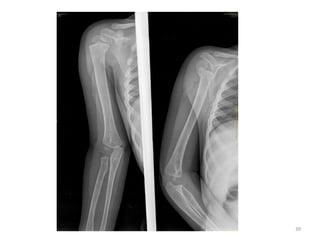

BONE OSSIFICATION CENTREAPPEARANCE CONJOINT EPIPHYSIS FUSION/UNION Clavicle Medial end 18-19 yrs - 20-22 yrs Sternum Manubrium& 1st piece 2nd & 3rd piece 4th piece xyphisternum 5th m of iul 7th m of iul 10th m of iul 3 yrs - All fuse from below upwards between 14 and 25 yrs Old age 40 yrs Scapula Coracoid process Acromion process 10-11 yrs 14-15 yrs 15-16 yrs 17-18 yrs Humerus Head Greater tuberosity Lesser tuberosity 1 3-4 yrs 5 5-6 yrs 18-19 yrs 20

• 21.

Elbow joint • Secondaryossification Centres : (3 bones; 6 Ocs) Capitulum (C) - appearance - 1 year of life Head of Radius (R)– appearance -4 to 5 years Medial Epicondyle (ME) Appearance – 5 to 6 years Fusion – 16 to 17 years Trochlea (T) – appearance – 9 to 11 years Olecranon Process of Ulna (OP) Appearance - 8 to 9 years Fusion- 16-17 years Lateral Epicondyle(LE) – 11 to 12 years Conjoint (Composite)Epiphysis (CE) [fusion of C+T+LE] Formation – 14 to 16 years Fusion – 16-17 years Note: Fusion of O.Centres at elbow joint is 16-17 years in male, 15-16 years in female 35